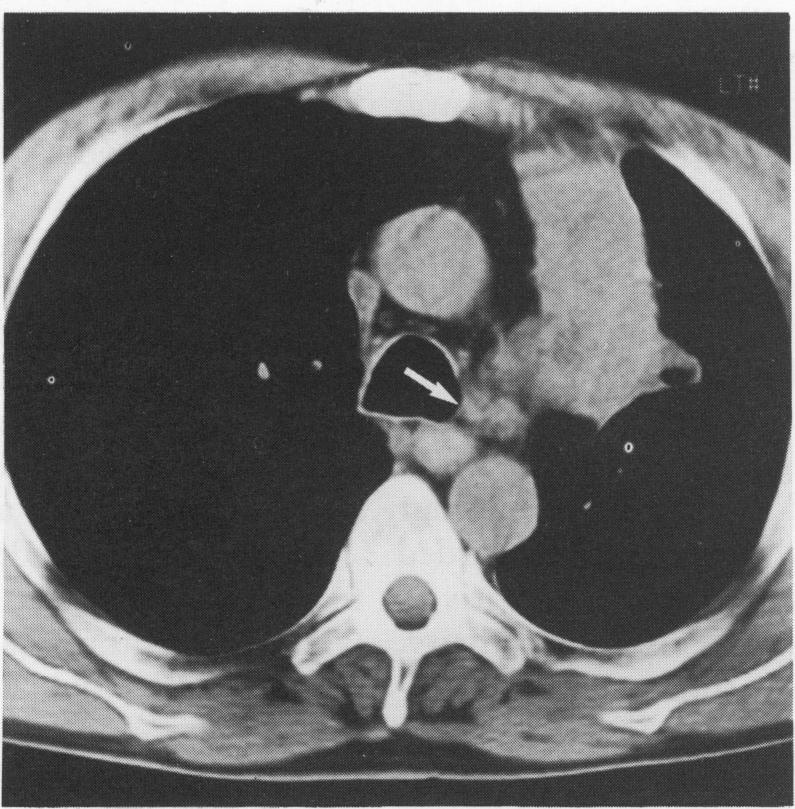

支气管癌的术前分期:计算机断层扫描能否可靠地识别Ⅲ期肿瘤?

Preoperative staging of carcinoma of the bronchus: can computed tomographic scanning reliably identify stage III tumours?

The aim of preoperative computed tomographic (CT) assessment of patients with carcinoma of the bronchus is to stage the tumour accurately, and forewarn the surgeon of any possible local extrapulmonary extension of tumour in patients considered to have potentially resectable disease. The ability of CT scanning to differentiate between conventionally resectable lung cancer (TNM stages I and II), locally advanced but resectable lung cancer (TNM stage IIIa), and locally advanced but unresectable lung cancer (TNM stage IIIb) was determined in a group of patients accepted for surgery.

METHODS

Computed tomographic scans of 110 patients who underwent thoracotomy for intended resection of carcinoma of the bronchus, including 52 cases with stage III and 58 cases with stage I or II disease, were reviewed and the CT features and radiological interpretations correlated with the surgical and pathological findings.

RESULTS

Thirteen CT scans were judged not to have been of diagnostic quality: of the remaining 97 cases 45 had stage III lung cancer, of whom 30 had successful resections, and 52 had stage I or stage II tumours. There was no difference in the frequencies of CT observations--including contiguity of tumour and mediastinum or chest wall, apparent mediastinal or chest wall invasion, proximity of tumour to the carina, mediastinal nodal enlargement, pulmonary collapse or consolidation and pleural effusion--in patients with stage I/II disease and patients with stage III disease. Similar results were found when the same observations were compared in all patients with resected disease and those with unresectable tumour. Sensitivity and specificity of CT was 27% and 96% respectively for tumour unresectability, 50% and 89% for mediastinal invasion, 14% and 99% for chest wall invasion, and 61% and 76% for mediastinal nodal metastases. Only 19 of 45 stage III tumours were correctly identified as being stage III and resectable or unresectable.

CONCLUSIONS

In patients being considered for thoracotomy for resection of lung cancer, CT scanning used as the sole method of staging is of limited value for differentiating between stage I/II and stage III tumours. Patients should not be denied the opportunity for curative surgery on the basis of equivocal CT signs.

对支气管癌患者进行术前计算机断层扫描(CT)评估的目的是准确对肿瘤进行分期,并在认为可能可切除的患者中,预先警告外科医生肿瘤任何可能的肺外局部扩展情况。在一组接受手术的患者中,确定了CT扫描区分传统可切除肺癌(TNM分期I期和II期)、局部晚期但可切除肺癌(TNM分期IIIA期)以及局部晚期但不可切除肺癌(TNM分期IIIB期)的能力。

方法

回顾了110例因计划切除支气管癌而接受开胸手术患者的CT扫描结果,其中包括52例III期患者和58例I期或II期患者,并将CT特征及影像学解释与手术和病理结果进行关联。

结果

13份CT扫描被判定诊断质量不佳:在其余97例病例中,45例为III期肺癌,其中30例成功切除,52例为I期或II期肿瘤。I/II期疾病患者和III期疾病患者在CT观察结果(包括肿瘤与纵隔或胸壁的连续性、明显的纵隔或胸壁侵犯、肿瘤与隆突的距离、纵隔淋巴结肿大、肺不张或实变以及胸腔积液)的频率上没有差异。在所有可切除疾病患者和不可切除肿瘤患者中比较相同观察结果时,也发现了类似结果。对于肿瘤不可切除,CT的敏感性和特异性分别为27%和96%;对于纵隔侵犯,分别为50%和89%;对于胸壁侵犯,分别为14%和99%;对于纵隔淋巴结转移,则分别为61%和76%。45例III期肿瘤中只有19例被正确判定为III期且可切除或不可切除。

结论

在考虑行开胸手术切除的患者中,仅将CT扫描用作分期方法在区分I/II期和III期肿瘤方面价值有限。不应基于不明确的CT征象而剥夺患者进行根治性手术的机会。